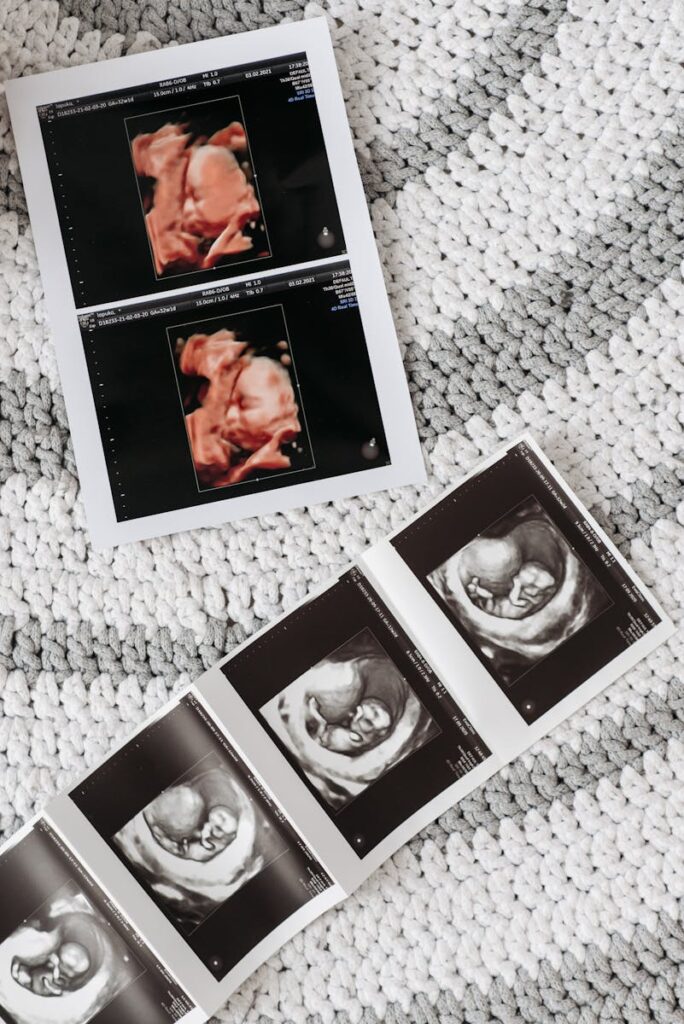

Co więcej – Twój maluszek ćwiczy już mięśnie mimiczne! Zmarszczki na czółku, grymasy, a nawet uśmiechy. Podczas USG połówkowego możesz złapać moment, gdy Twoje dziecko robi zabawną minkę.

U Adasia w 18 tygodniu na USG zobaczyliśmy, jak ssie kciuk. Lekarka powiedziała: “Patrz, trenuje do karmienia!”. I rzeczywiście – po urodzeniu od razu wiedział, co robić z piersią.

U nas płeć poznaliśmy właśnie w 18 tygodniu. Lekarka powiedziała z uśmiechem: “No, to będzie chłopiec!”. Pamiętam, jak spojrzeliśmy z mężem po sobie i oboje wybuchnęliśmy śmiechem ze szczęścia. Od tego momentu przestałam mówić “dziecko” – zaczęłam mówić “Adaś”.

A teraz najważniejsza część 18 tygodnia ciąży – USG połówkowe. To jedno z dwóch najważniejszych badań ultrasonograficznych w całej ciąży (obok USG genetycznego w I trymestrze).

Zalecany czas: między 18. a 22. tygodniem ciąży (dokładnie: 18+0 do 22+6)

Najlepszy moment: między 20. a 22. tygodniem

Dlaczego nie wcześniej? W 18 tygodniu dziecko może być jeszcze zbyt małe, żeby lekarz mógł dokładnie ocenić wszystkie struktury – szczególnie serce i twarz. Z każdym tygodniem wizualizacja jest lepsza.

Dlaczego nie później? Po 22 tygodniu dziecko rośnie tak szybko, że trudniej jest je “zobaczyć” w całości.

U mnie USG połówkowe było w 20 tygodniu. Lekarka powiedziała, że to optymalny moment – dziecko jest już wystarczająco duże, żeby wszystko dokładnie zobaczyć, ale wciąż ma miejsce, żeby się obracać.

Co sprawdza lekarz podczas USG połówkowego?

Moje wspomnienia z USG połówkowego

Pamiętam ten dzień bardzo wyraźnie. Byłam strasznie zdenerwowana – co jeśli będzie coś nie tak? Ale gdy tylko zobaczyłam Adasia na ekranie, wszystkie obawy zniknęły.

Był tam – małe, doskonałe stworzenie. Lekarka pokazywała nam każdy szczegół: “Tu jest serduszko, teraz liczymy paluszki u nóżek, a tu – widzi Pani? – ssie kciuk!”.

Płakałam. Mąż płakał. To było niesamowite uczucie – zobaczyć, że nasze dziecko jest zdrowe, rozwija się, żyje swoim życiem w moim brzuchu.

Dostaliśmy kilka zdjęć z USG i do dziś je mam – Adaś uwielbia je oglądać i pyta: “To ja byłem w brzuchu?”.